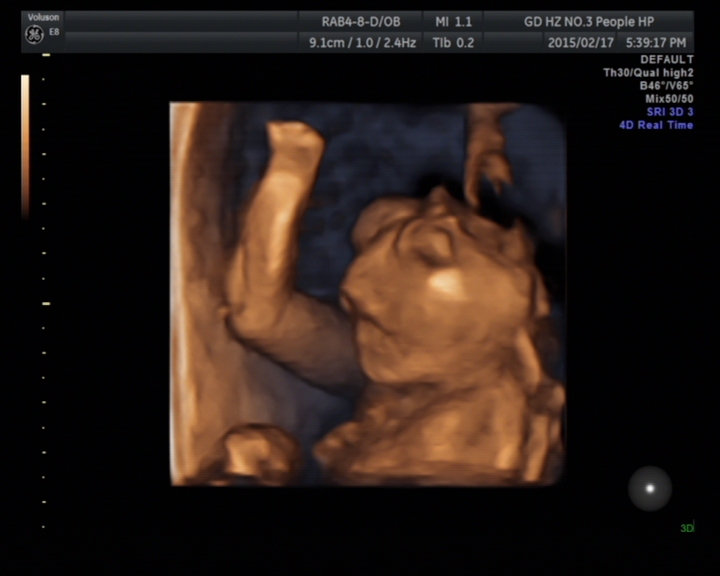

故事發(fā)生于2015217號(hào)(年廿九)下午,一對(duì)年輕的夫婦滿臉笑容地向超聲科走來(lái),準(zhǔn)媽媽?xiě)言屑s21周,來(lái)醫(yī)院做胎兒彩超檢查,想著明天回家開(kāi)開(kāi)心心過(guò)新年。誰(shuí)知道天有不測(cè)風(fēng)云,張春云副主任醫(yī)師在檢查中發(fā)現(xiàn)胎兒患有先天性畸形——無(wú)腦兒、復(fù)雜性心臟畸形、唇腭裂。就在那一瞬間,一切都變了,她哭了,他也變得心情沉重,臉上也失去了笑容。

無(wú)腦畸形是指胎兒顱蓋骨缺失。具體病因不明,可能與脊柱裂相似,也是多因素致病,包括遺傳、環(huán)境、致畸因子如射線、水楊酸鹽、磺胺等。無(wú)腦兒表現(xiàn)為無(wú)顱蓋、無(wú)大腦,僅見(jiàn)顱底或顱底部分腦組織,雙眼眶位于最高處,無(wú)額骨顯示,呈“青蛙”狀面容。無(wú)腦兒一般不能存活,少數(shù)生出來(lái)后能存活幾個(gè)小時(shí)或一天。因此,一旦超聲明確診斷,將立即終止妊娠。